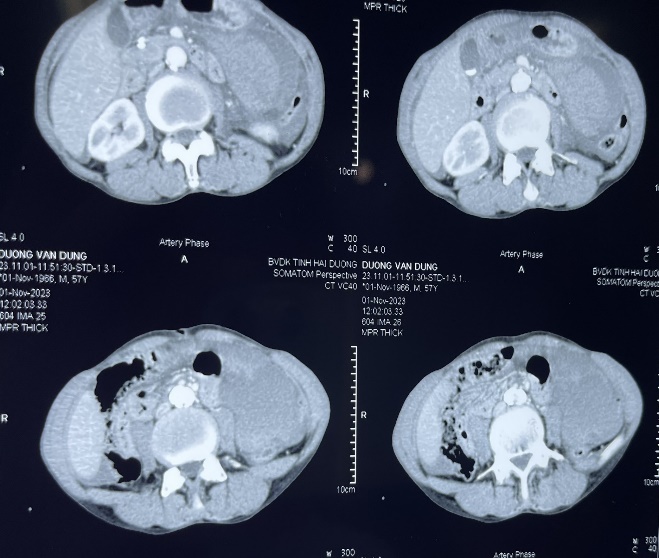

NHÂN MỘT TRƯỜNG HỢP CHẤN THƯƠNG TỤY

Chấn thương tụy là một chấn thương hiếm gặp nhưng có khả năng gây tử vong cao và rất khó chẩn đoán. Các phương pháp hình ảnh thông thường hay bỏ sót những tổn thương tinh tế liên quan đến chấn thương tuyến tụy.